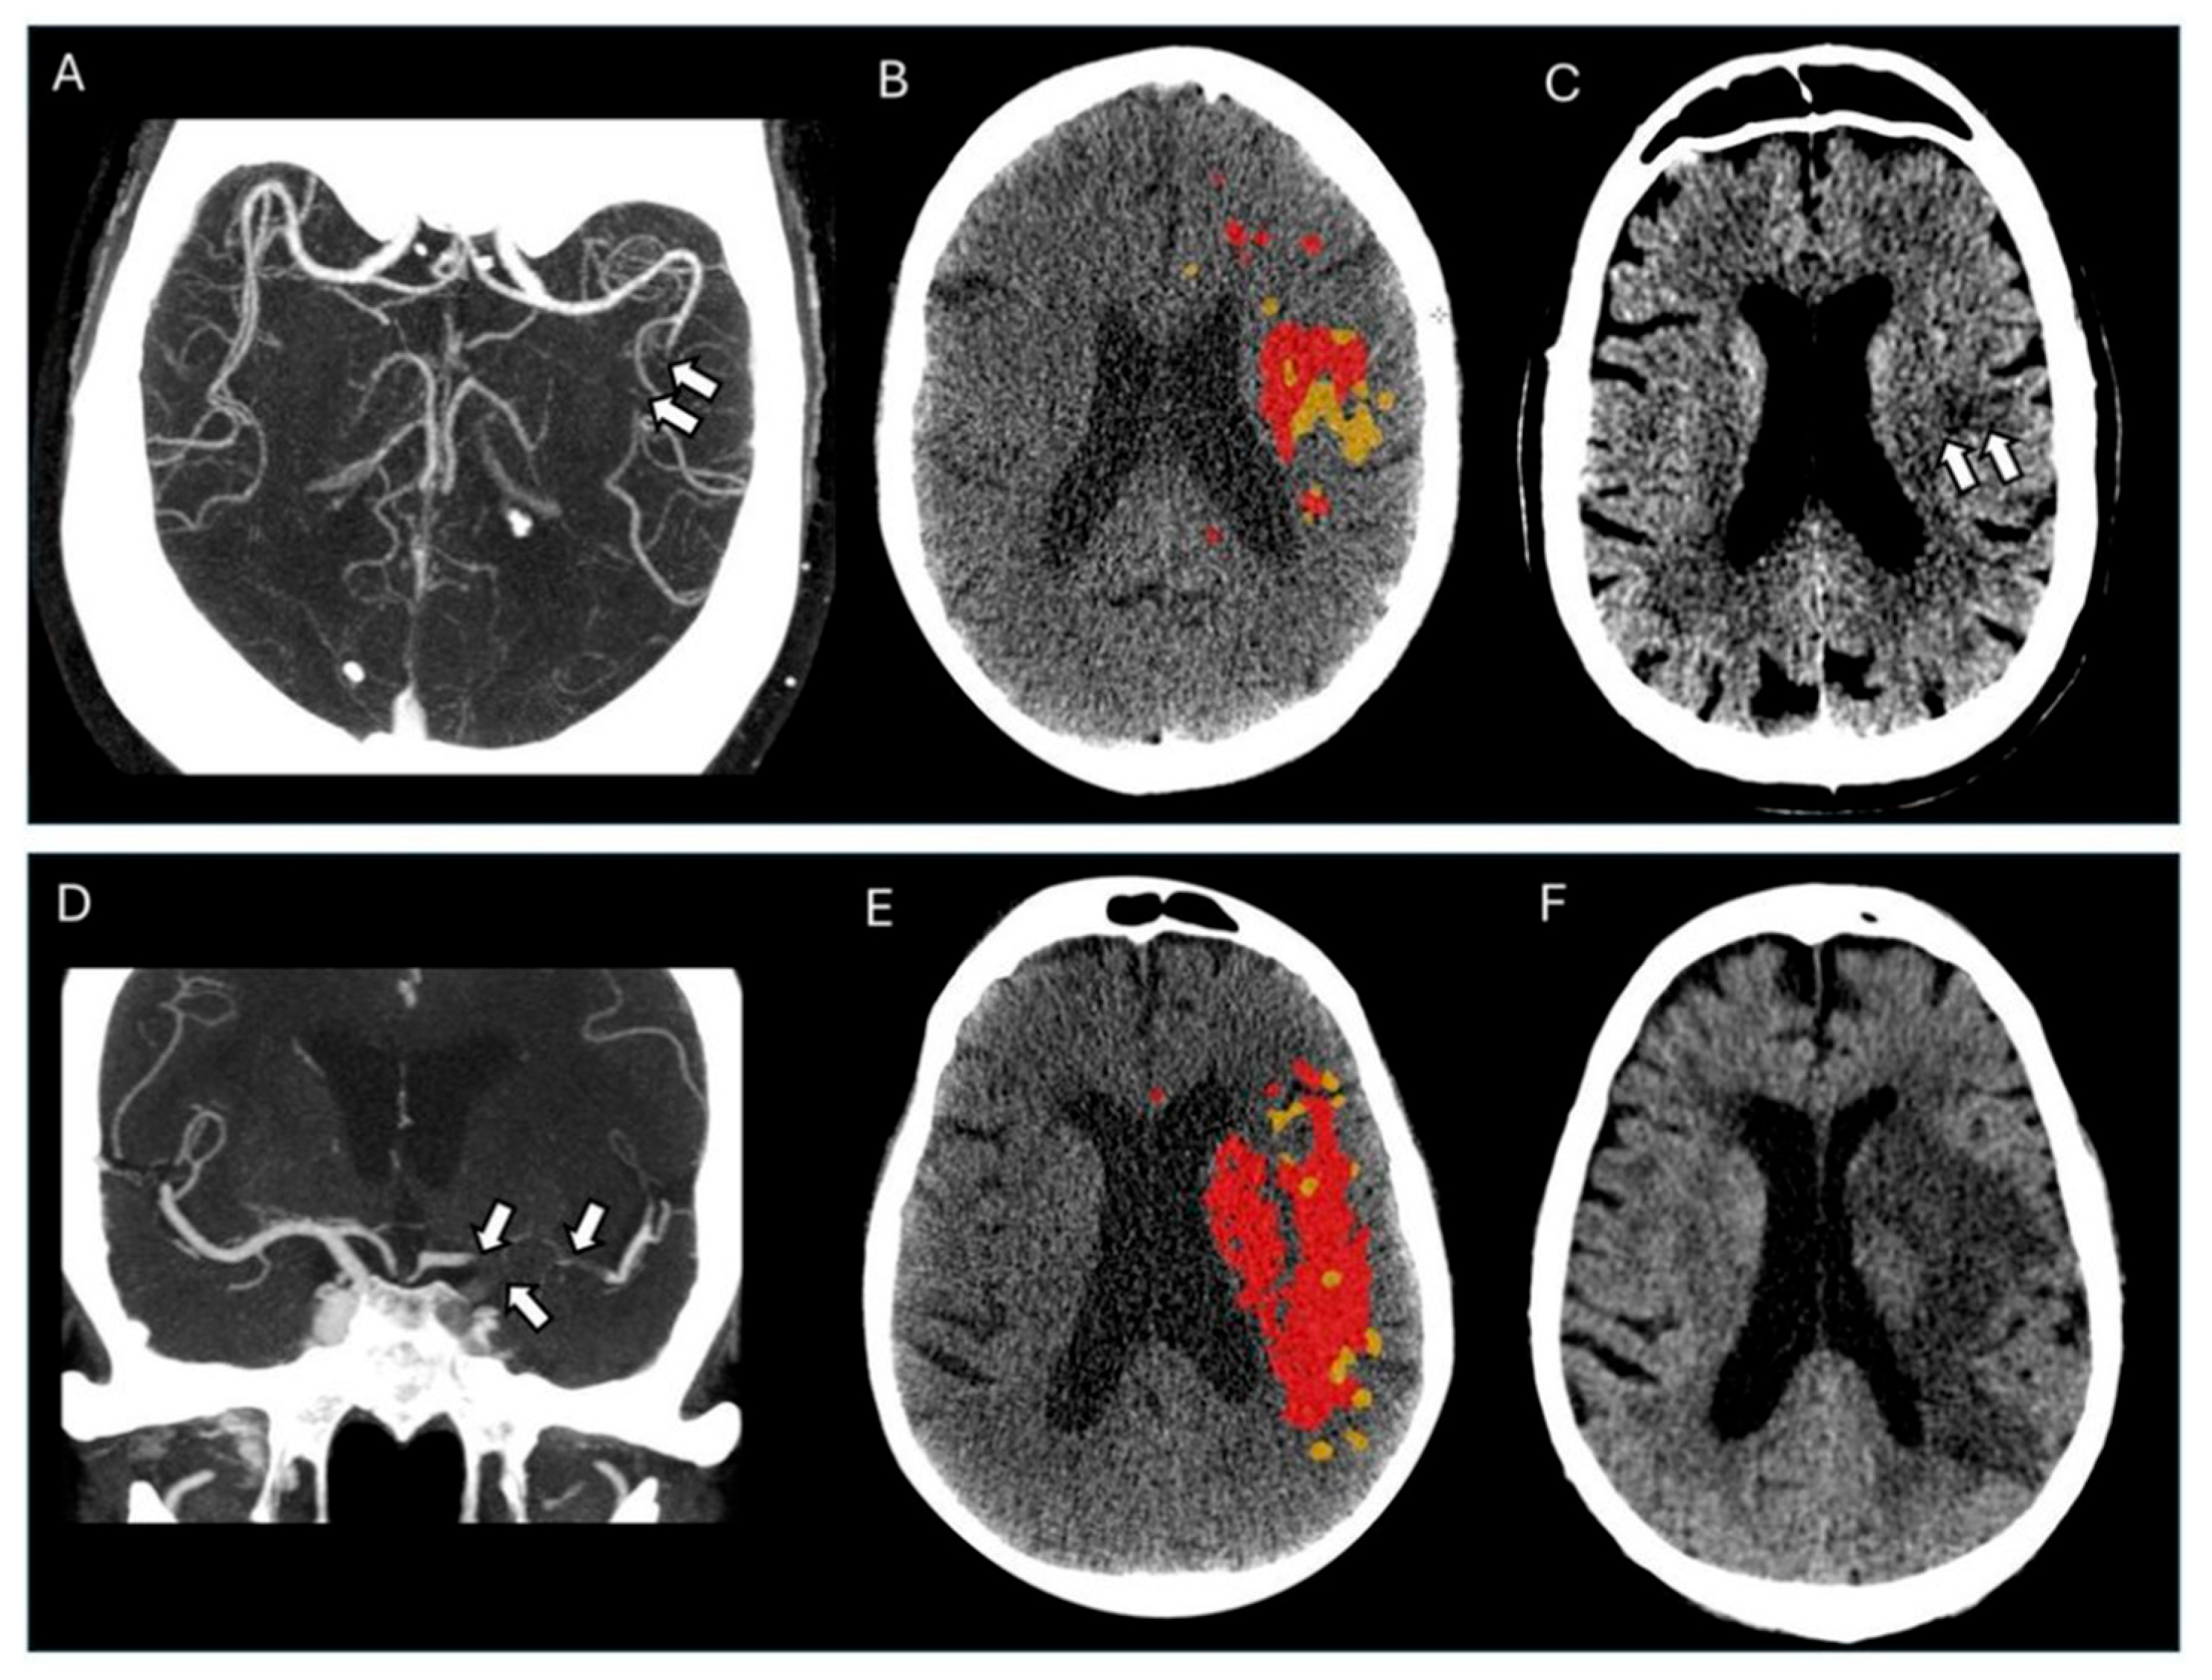

2.2. Imaging Protocol and Analyses

3. Results

3.2. Outcome Analyses

4. Discussion